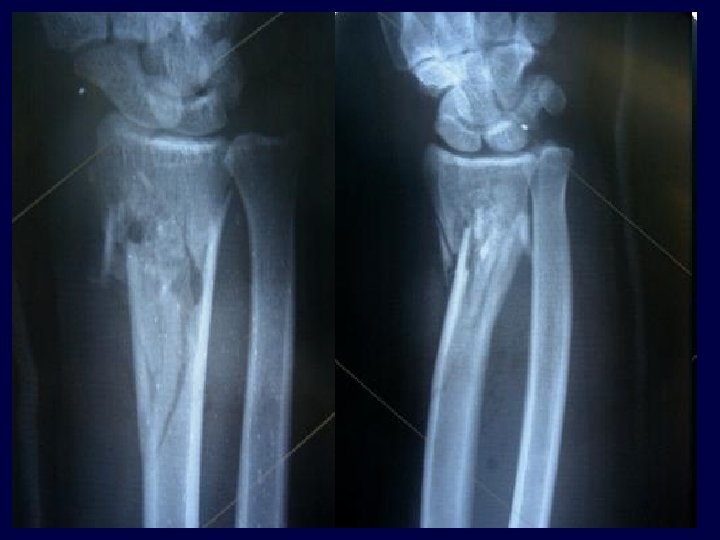

• 28 y. o. male • Shotgun load with large pellets • Neuro intact • Vascular intact • Large lateral wound from close range injury • Exploration – Wadding, packing and pellets, all removed • Repeat debridement at 72 hours

• Significant comminution not appreciated pre-op – Head split present • ORIF performed

• Significant bone loss and muscle damage from energy of Shotgun • Treated as open fracture with multiple debridements

• Healed at three months • Motion limited – No active Abduction due to injury to rotator cuff insertion